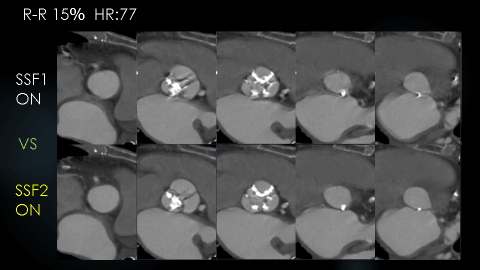

下図はHR77の高心拍の症例で、SSF2.0と第一世代のSSF1.0での駆出期の画像の比較です。SSF1.0ではどの位相でもモーションアーチファクトが残存しています。 SSF2.0導入後は、どの位相においても(図1)、またどの断面においても(図2)、モーションアーチファクトが抑制された画像が得られていました。

RevolusionCT_OguraKinen_10.png

RevolusionCT_OguraKinen_11.png

図1 Annulus断面の比較

RevolusionCT_OguraKinen_12.png

図2 STJからLVOT断面までの比較